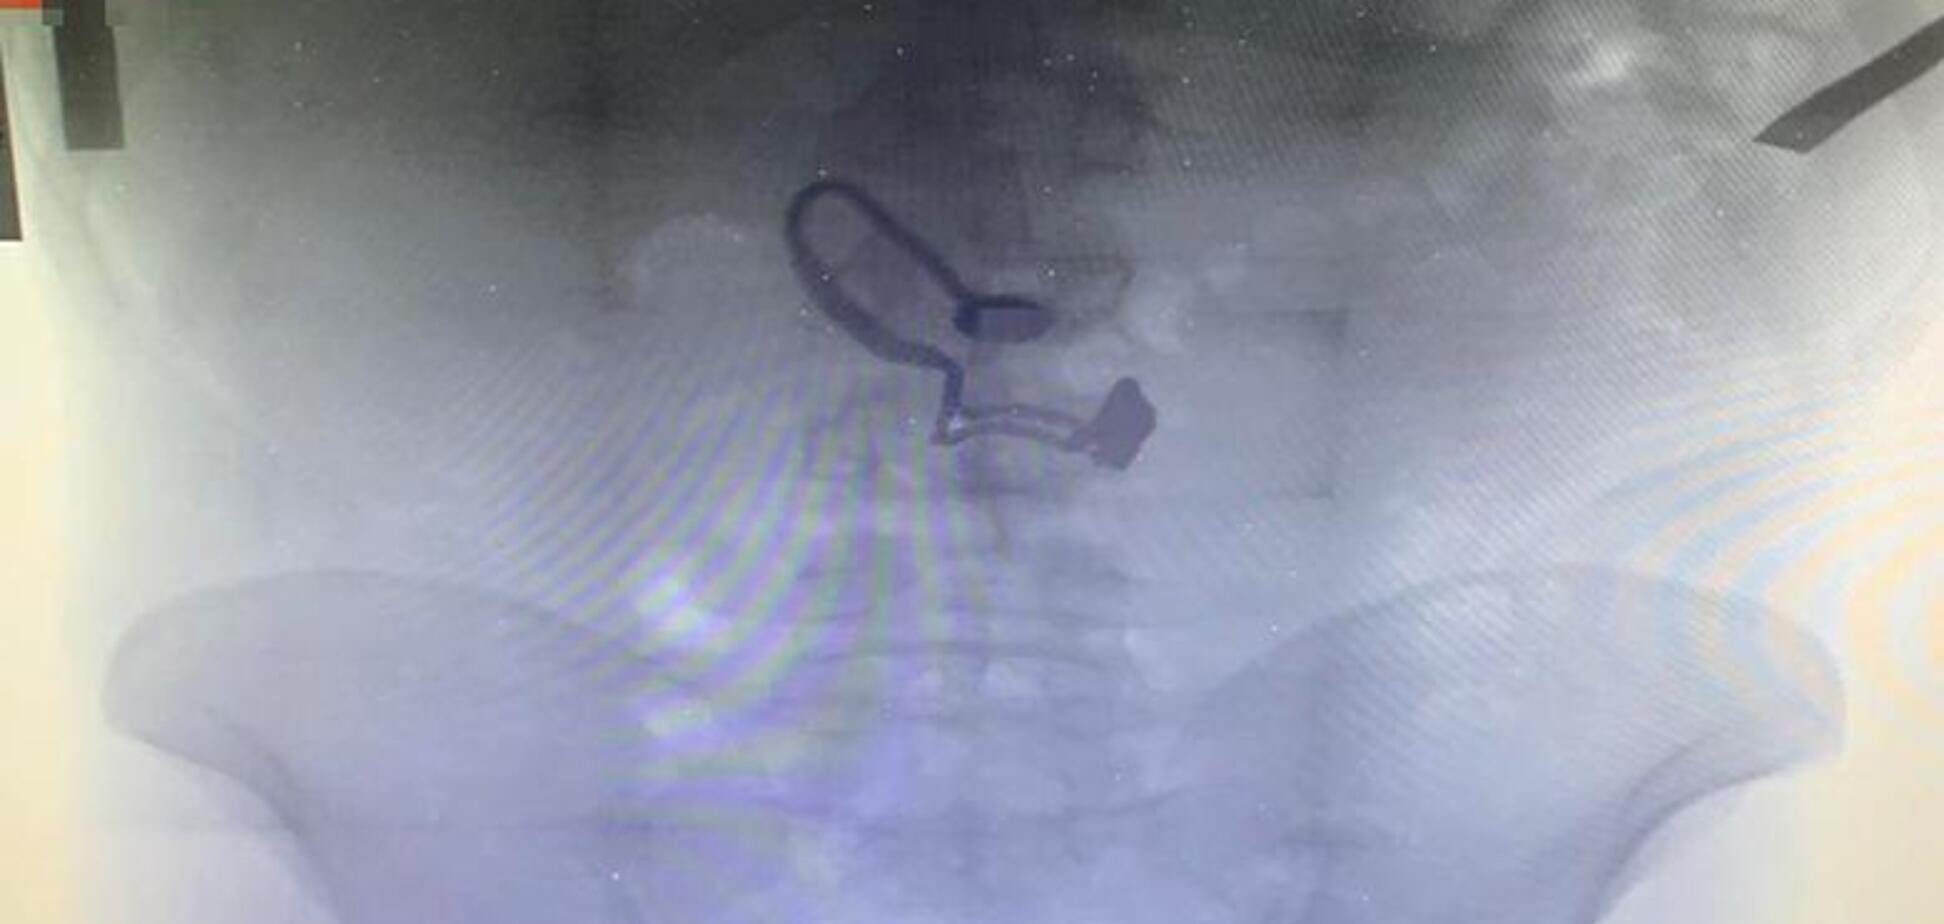

Во время обыска у мужчины нашли кошелек пострадавшей, а золотую цепочку он проглотил еще во время побега от очевидцев. Украшение в желудке грабителя определили на рентгене.